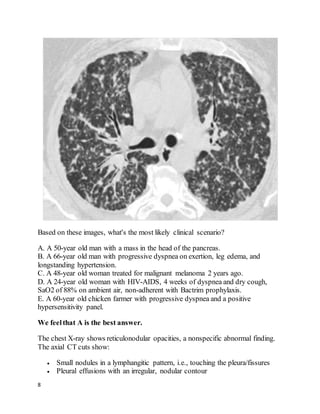

Based on these images, what's the most likely clinical scenario?

A. A 50-year old man with a mass in the head of the pancreas.

B. A 66-year old man with progressive dyspnea on exertion, leg edema, and

longstanding hypertension.

C. A 48-year old woman treated for malignant melanoma 2 years ago.

D. A 24-year old woman with HIV-AIDS, 4 weeks of dyspnea and dry cough,

SaO2 of 88% on ambient air, non-adherent with Bactrim prophylaxis.

E. A 60-year old chicken farmer with progressive dyspnea and a positive

hypersensitivity panel.

We feelthat A is the best answer.

The chest X-ray shows reticulonodular opacities, a nonspecific abnormal finding.

The axial CT cuts show:

 Small nodules in a lymphangitic pattern, i.e., touching the pleura/fissures

 Pleural effusions with an irregular, nodular contour

 Irregular thickening of the interlobular septa

 Peribronchovascular thickening

All these findings are consistent with this patient's diagnosis of lymphangitic

carcinomatosis(LC): diffuse metastatic spread of cancer to the lungs, where it

diffusely infiltrates and obstructs lymphatic channels. 80% of cases are due to

adenocarcinomas, most often from a primary cancer of the breast, lung, or colon.

This case of LC was from a primary pancreatic adenocarcinoma.

Chest films are usually normal in lymphangitic carcinomatosis.